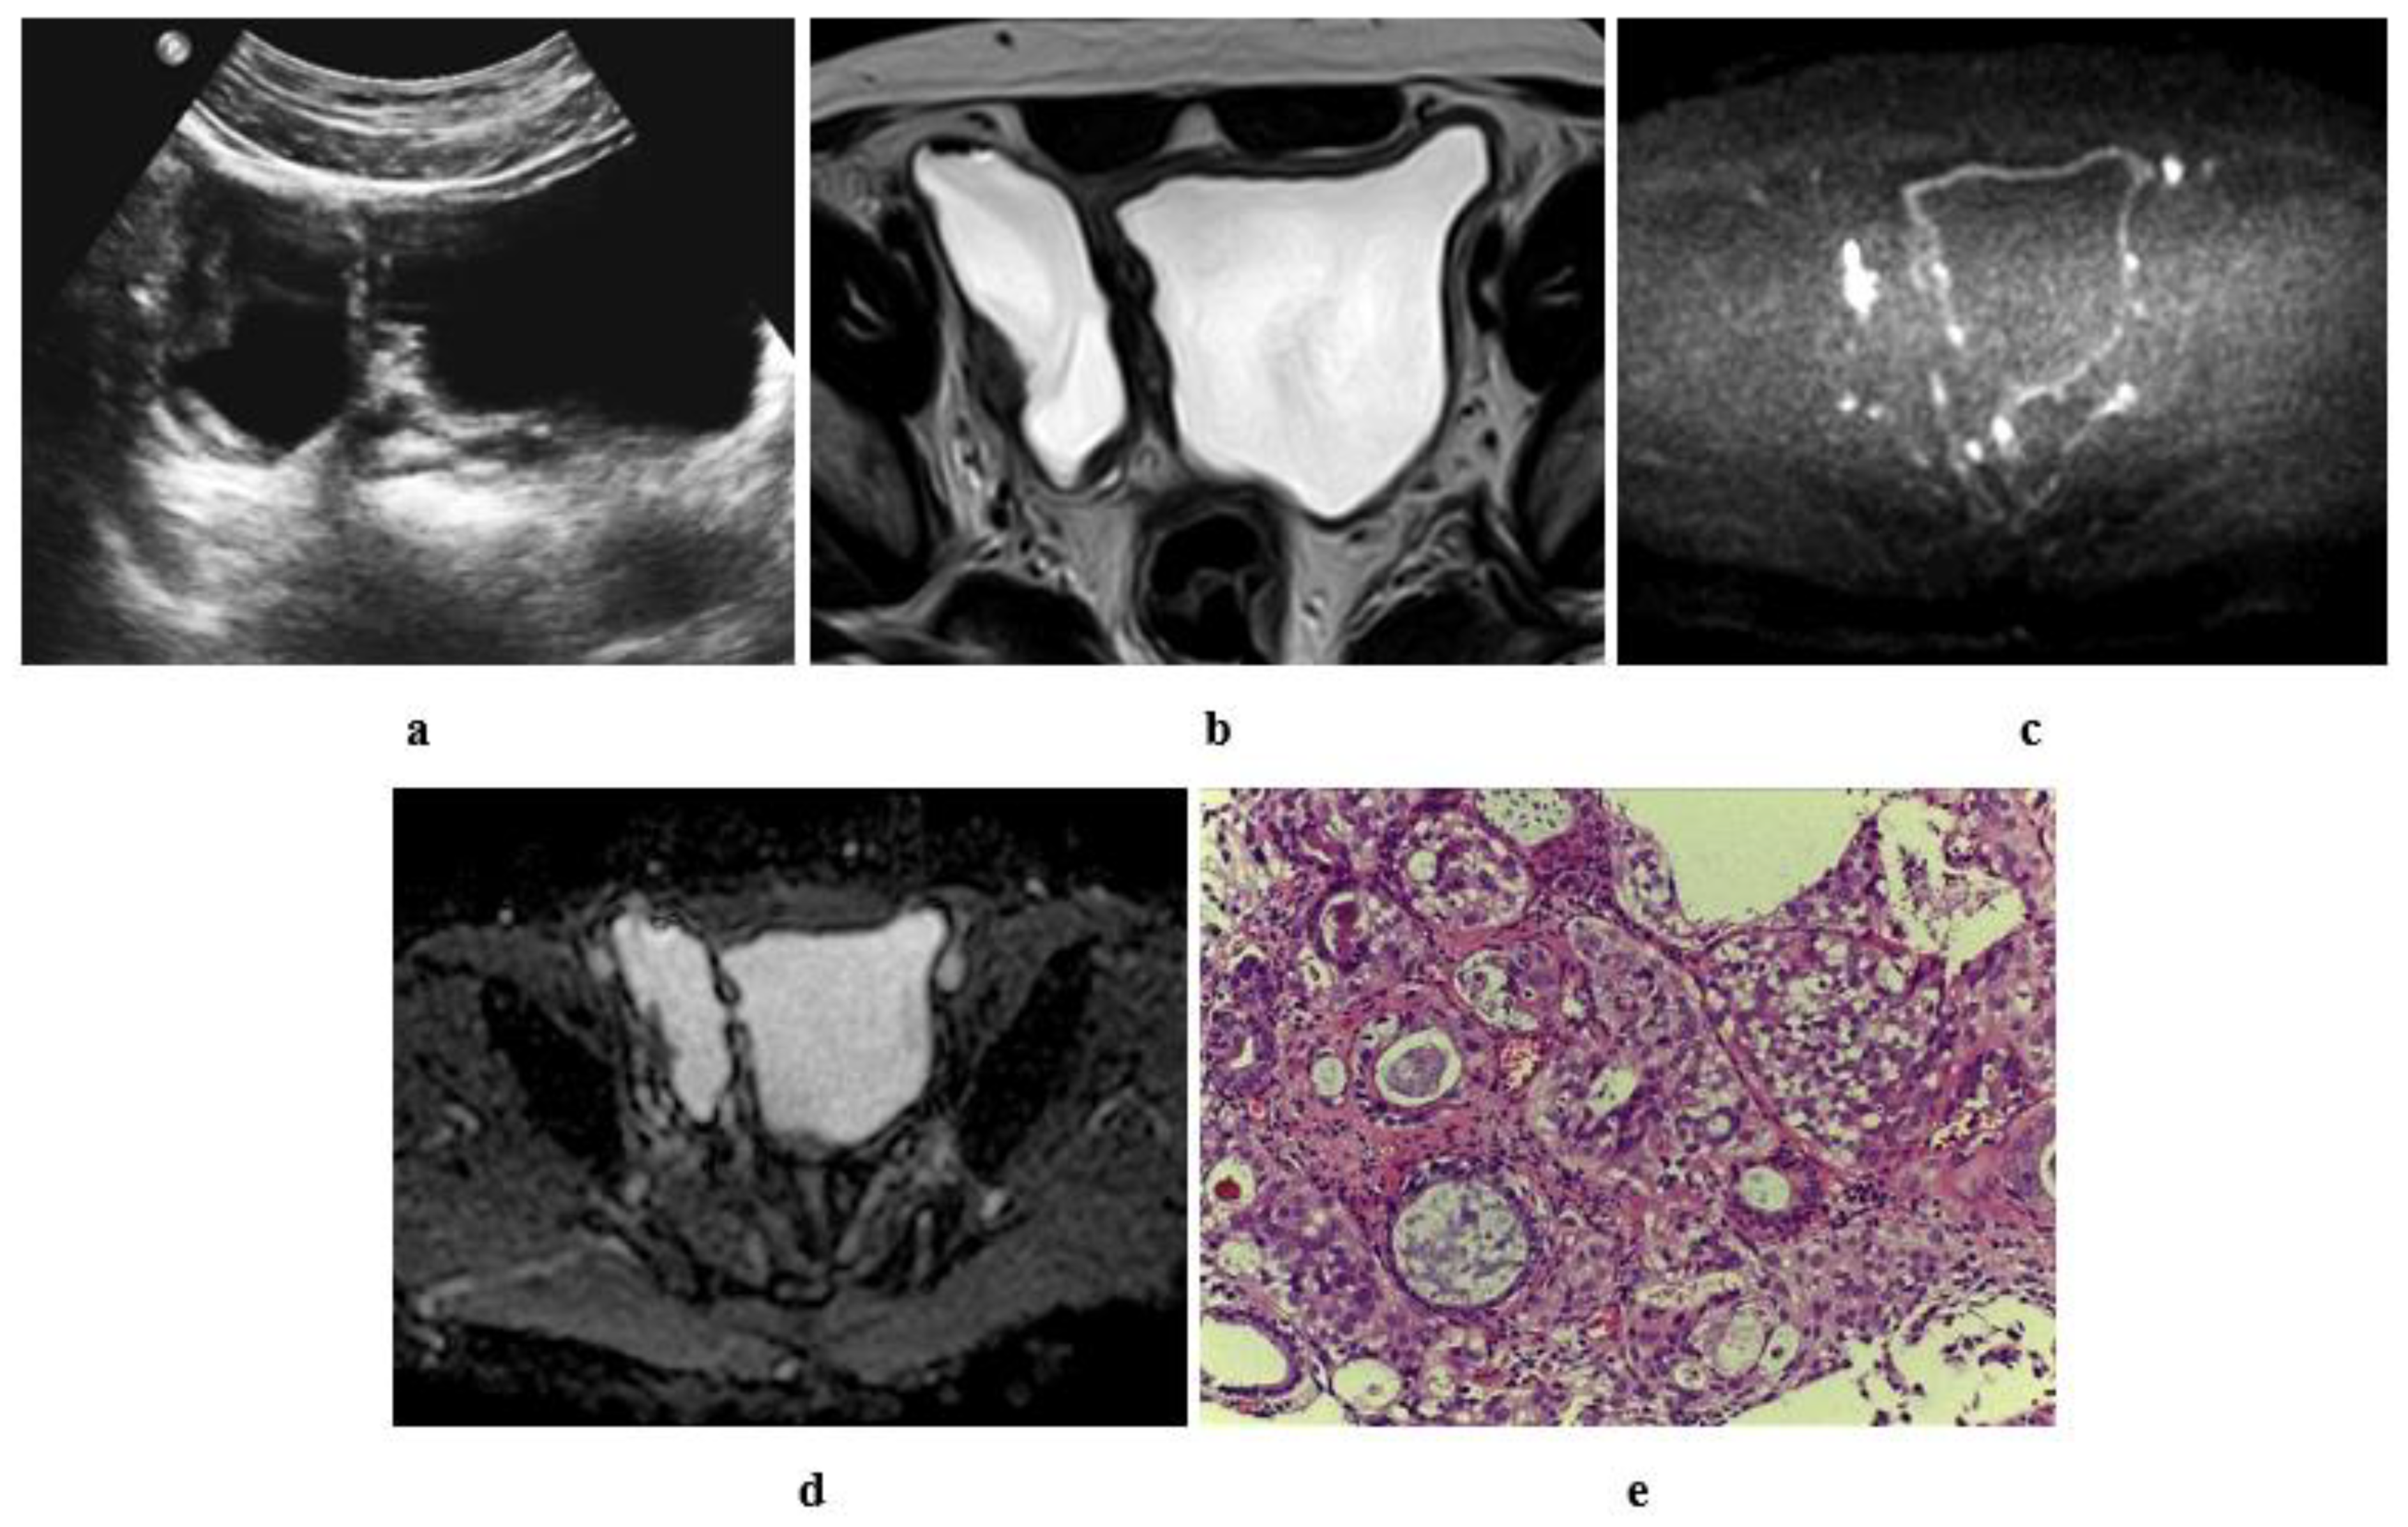

Accounts for around 3-8 of all bladder cancers. The role of newer MR imaging. Whole-body CT is the primary imaging technique for detecting metastases in affected patients especially those with muscle-invasive disease.

Leiomyosarcoma is a rare type of cancer that affects smooth muscle tissue. MRI can distinguish muscle-invasive from non-muscle-invasive tumors with accurate local staging. Magnetic resonance MR imaging and computed tomography CT were compared in 30 patients with histologically proved bladder cancer.

Bladder cancer is a broad term used to describe all types of cancers affecting the urinary bladder. Staging can be performed with CT but distinguishing between T1 and T2 BCa bladder cancer cannot be assessed. Squamous cell carcinoma urinary bladder.

Conventional CT and MR imaging are only moderately accurate in the diagnosis and local staging of bladder cancer. Urothelial Carcinoma of the Bladder. 1 The man-agement of bladder cancer is determined predominantly by stage and grade of disease at diagnosis.

This review will discuss the standard application novel imaging modalities and their additive role in patients with bladder cancer.